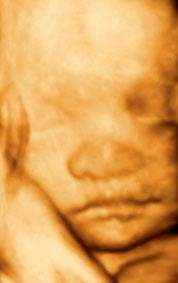

香港结构超声波照片

结构性超声波, 四维 香港, 四维结构性超声波 结构性超声波, 四维 结构性超声波, 四维 香港, 四维结构性超声波 结构性超声波, 四维 香港, 四维结构性超声波 结构性超声波, 四维 结构性超声波, 四维 结构性超声波, 四维 香港, 四维结构性超声波 结构性超声波, 四维 香港, 四维结构性超声波 结构性超声波, 四维 结构性超声波, 四维